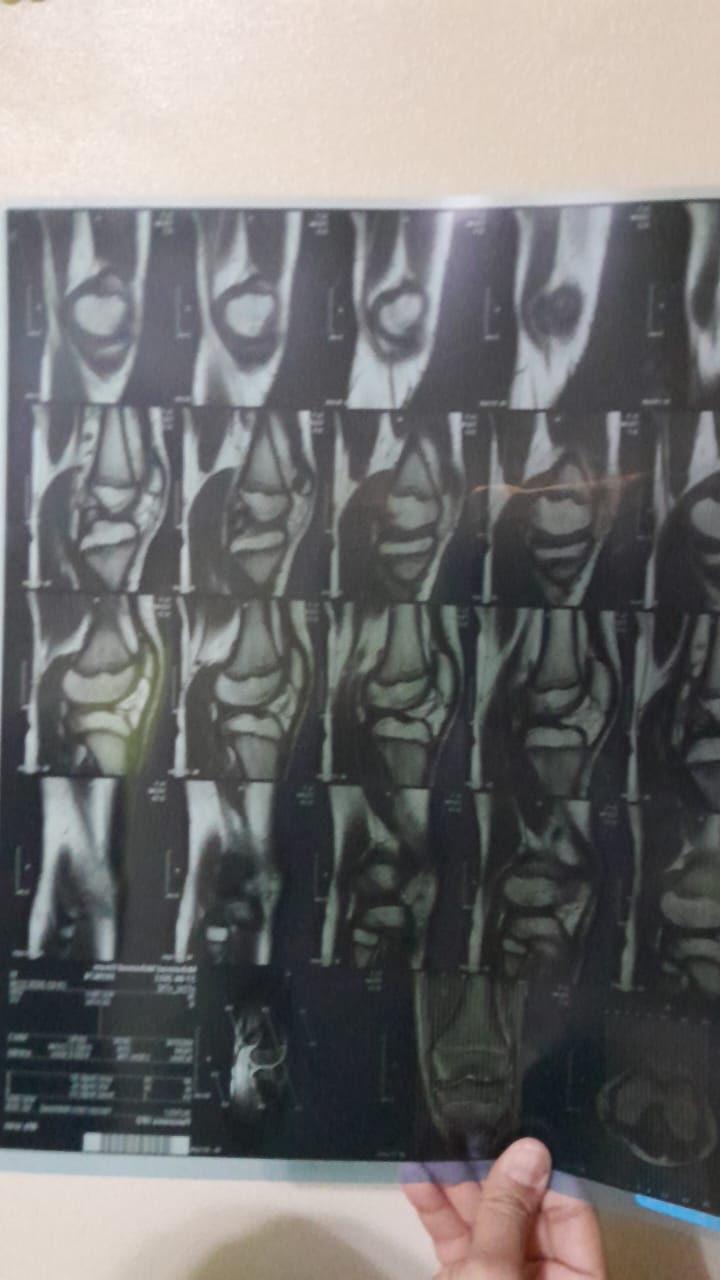

وأضاف والد الطفل مهند،م: اللي حصل إننا بقالنا 3 شهور تقريبا ابني عنده قطع في غضروف الركبة ورباط صليبي، وروحت لدكاترة كتير عشان أشخص الحالة وأنفقت أموالا طائلة، واستقريت على طبيب شهير (إبراهيم، ج) لعمل الجراحة وهو طبيب مشهود له بالكفاءة في التخصص، ولكنه يجري الجراحات في مستشفيات معينة ومحددة، منها مستشفى ABC، وبالفعل عند تقديم طلب لإدارة التعاقدات بمقر عملي بالمصرية للاتصالات تعاونت الإدارة على الفور وأنهت جميع الإجراءات سريعًا وراسلت إدارة مستشفى ABC موضحة أنها متحملة كافة النفقات، وحدد الطبيب موعدا للجراحة أمس، وجاء بالفعل بعد تجهيز ابني بالصيام والمتعارف عليه طبيًا ولكن الجراح فوجئ بوجود خامات تؤثر سلبا على فرص نجاح العملية بنسب عالية ونوعية رديئة، خصوصا ان الطفل يحتاج إلى جراحتان واحدة بالغضروف والأخرى بالرباط الصليبي.